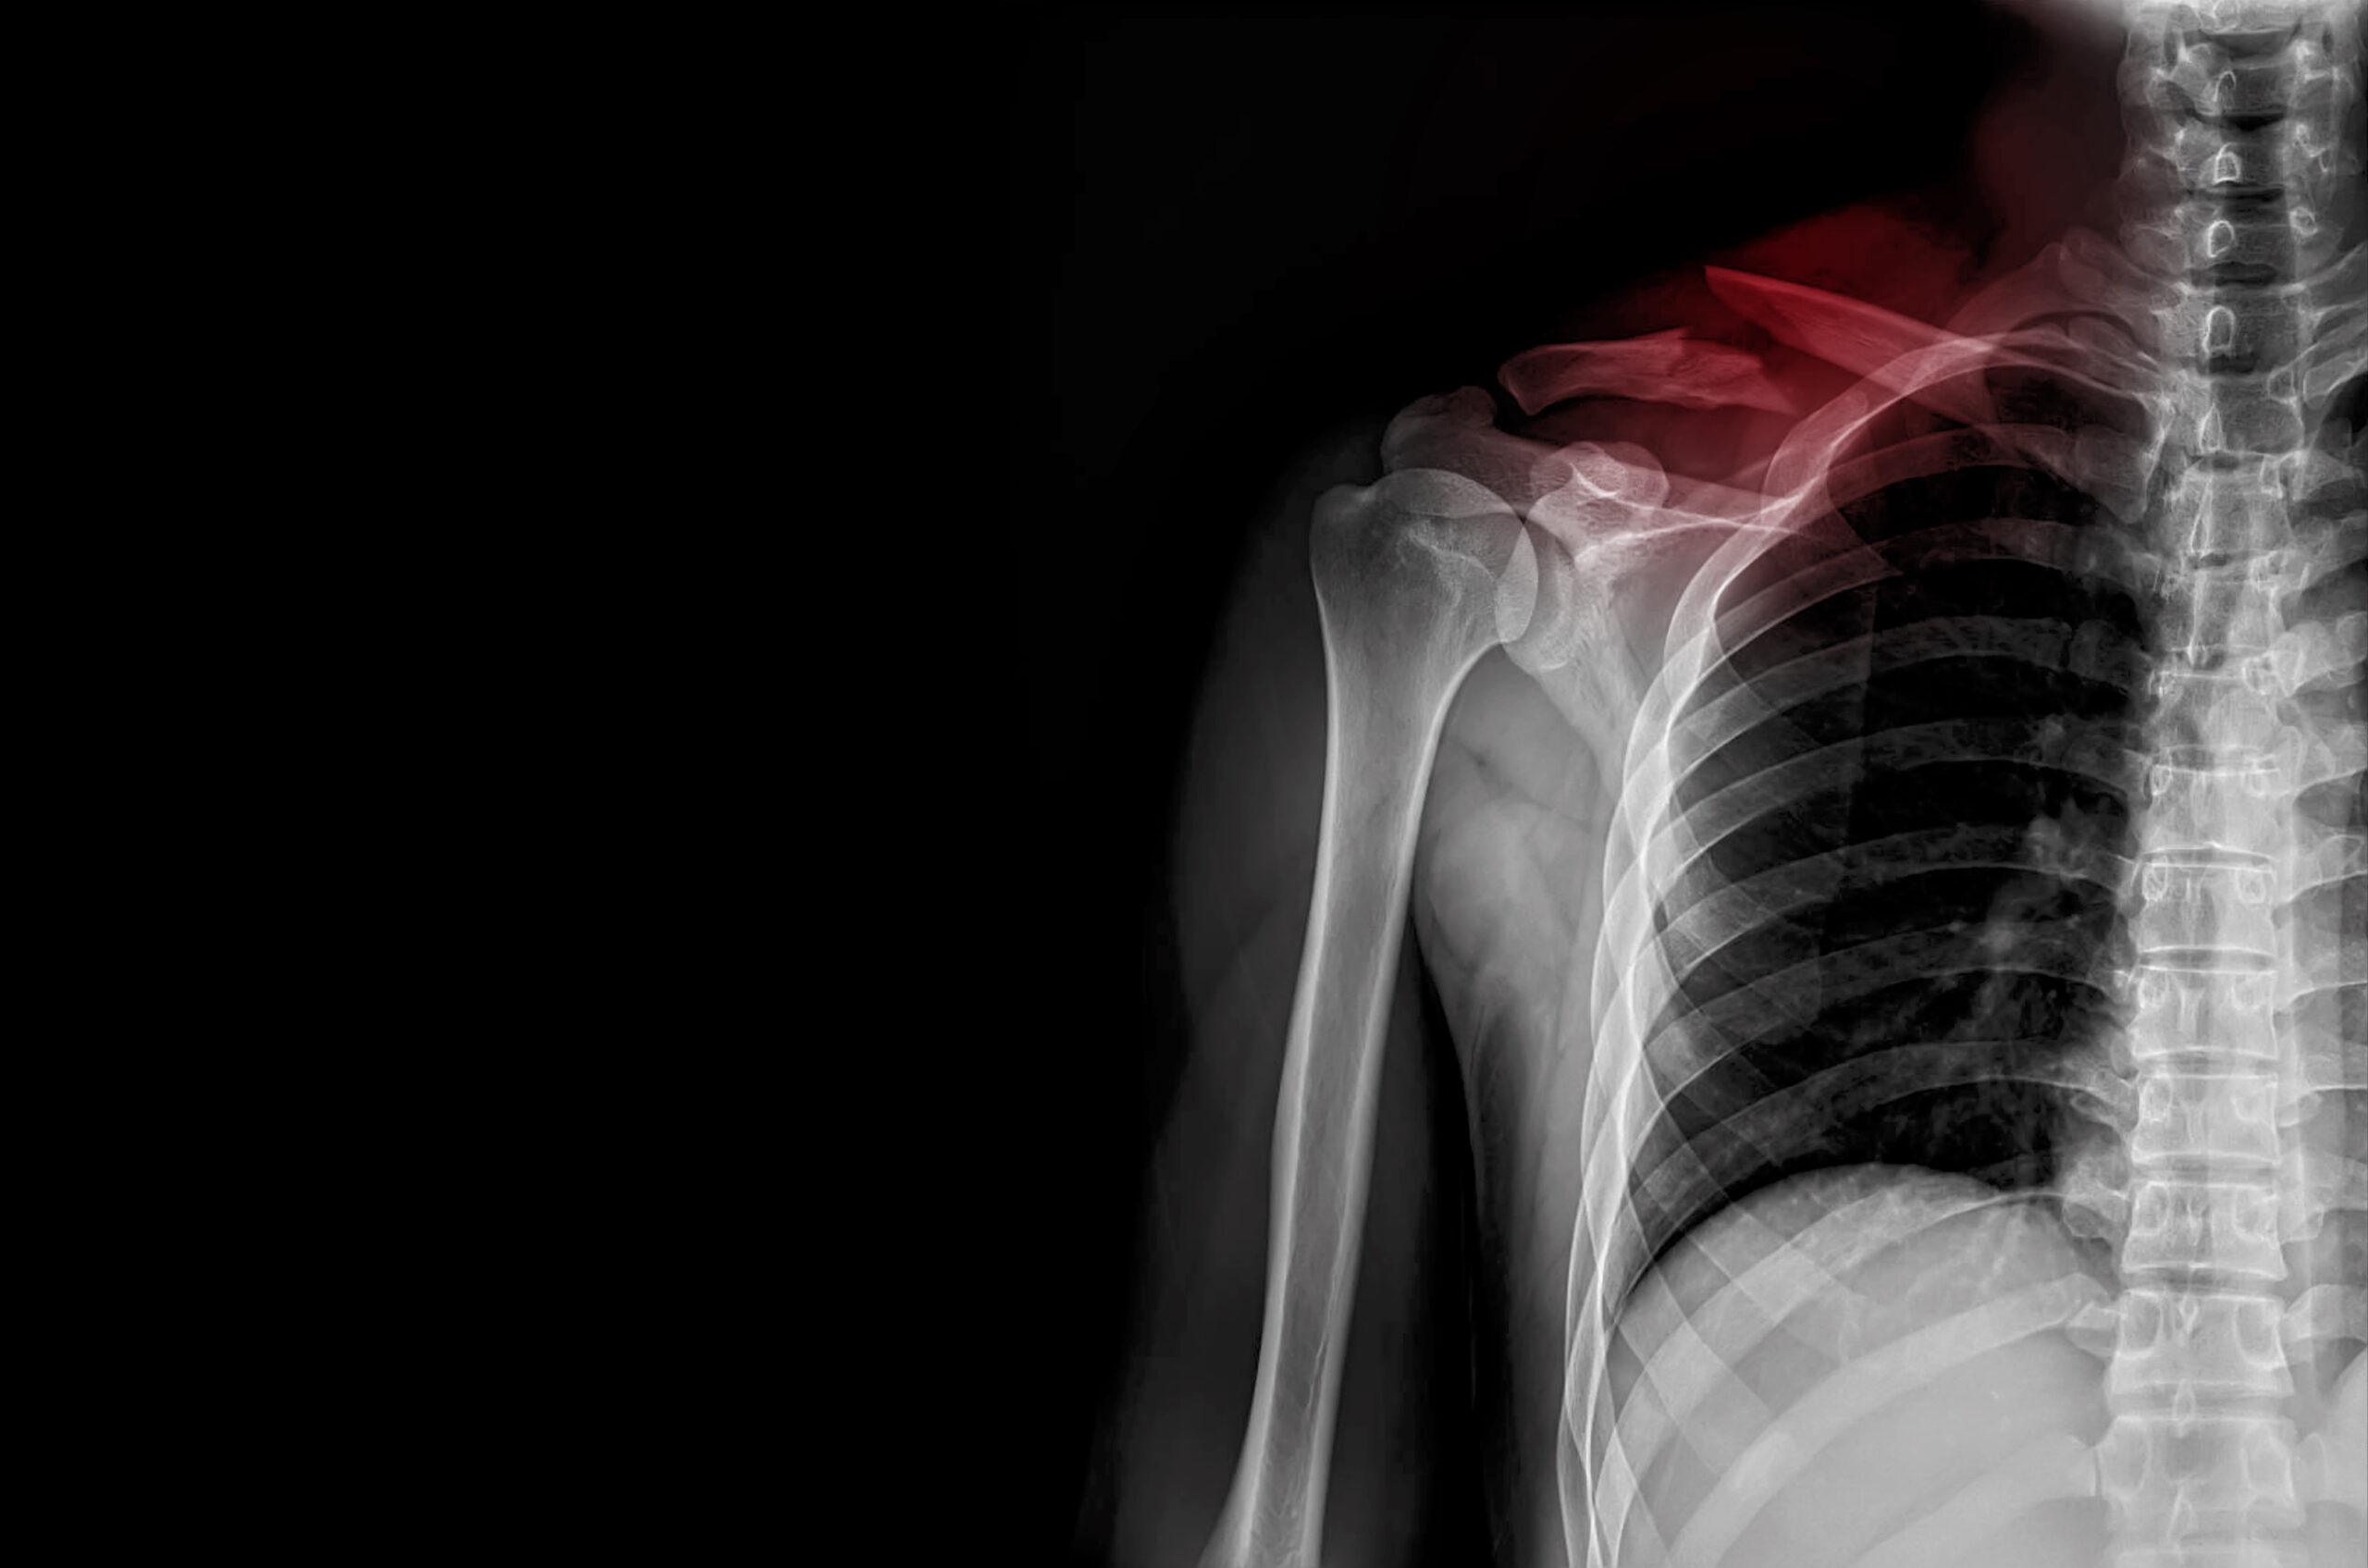

ただし、全てが筋由来とは限りません。頚椎の退行性変化がある場合、椎間板の水分喪失や骨棘が基盤となり、急性負荷で椎間関節包が刺激されて炎症様疼痛を誘発します。高齢者や長年の不良姿勢習慣がある人では、このパターンが潜伏しやすく、「いつもの寝違えのはずが長引く」ケースに発展します。炎症主体なら安静時痛や熱感が加わり、神経根圧迫の兆候として手への放散痛も見られます。こうした鑑別は、触診に加え可動域テストや神経学的検査で可能ですが、画像診断は急性期では過剰です。むしろ、機能的アセスメントで肩甲骨の挙上・後退パターンを確認すると、深層筋の関与が明らかになります。例えば、肩甲骨内転筋の弱さが頚部負荷を増大させるという知見は、肩甲骨アライメント研究から裏付けられています。